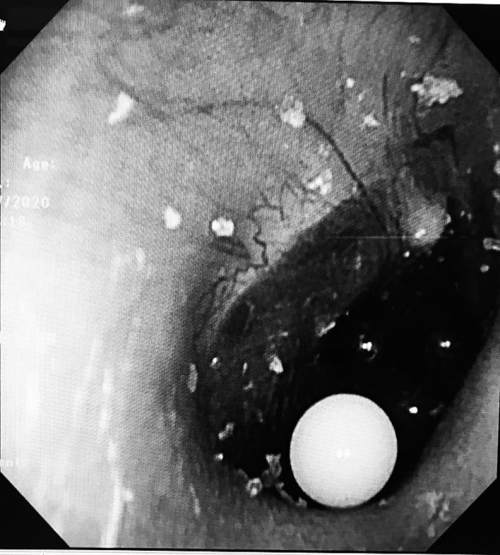

了解了情况后,医生为淘淘做了电子耳内窥镜检查,发现淘淘的右耳内有4颗彩色的小圆粒,位置都贴近了鼓膜,而且小圆粒填满了耳道。因为这是吸水弹珠,医生平时在门诊用的常规无创水冲洗法不可行,最终只能在全麻的情况下,为淘淘进行异物取出术。

手术开始两分钟后,离鼓膜最远的白色弹珠被顺利取出。“第一颗取得还算顺利,但是取另外3颗就有点困难了,剩下的3颗小珠子相互挤压,与耳道壁及鼓膜紧密接触,我们只能用耵聍钩从珠子前方、下方寻找缝隙,从里往外将弹珠带出。”李莉萍说,经过一番努力,剩下的3颗弹珠也被顺利取出。